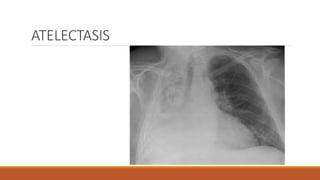

ATELECTASIS